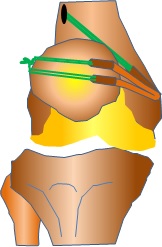

再建方法は、本来の内側膝蓋大腿靭帯の骨への付着部に骨孔(トンネル)を作成して、移植腱を挿入します。移植する腱は内側ハムストリング腱(主に半腱様筋腱)を使用しますが、採取による筋力低下などの合併症はほとんど認めません。移植腱の固定にはチタン合金性の小さなボタンを用います。

再脱臼予防には有効な治療法です。いろいろな手術方法がありますが自分の腱を移植して損傷した内側膝蓋大腿靭帯を再建(もう一度作り直すこと)する方法が近年注目されています。ほかの手術方法に比べると再脱臼の頻度がかなり低く、術後のリハビリ期間も短くなっています。

<手術治療>